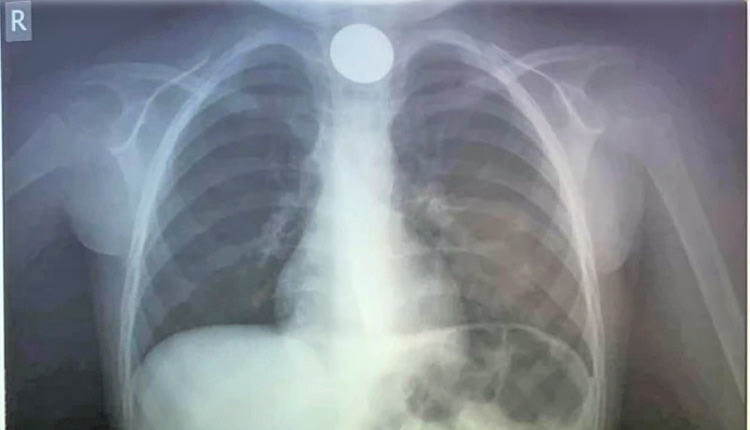

Όταν το παιδί έφτασε στο ΠΑΓΝΗ, οι γιατροί έκαναν ακτινογραφία για να δουν σε ποιο σημείο ακριβώς είχε σταθεί το νόμισμα και αμέσως μετά προχώρησαν στη διαδικασία αφαίρεσής του. Δεν πέρασε πολύς χρόνος και οι γιατροί κατάφεραν να αντιμετωπίσουν επιτυχώς το επείγον περιστατικό, λύνοντας ταχύτατα το πρόβλημα.